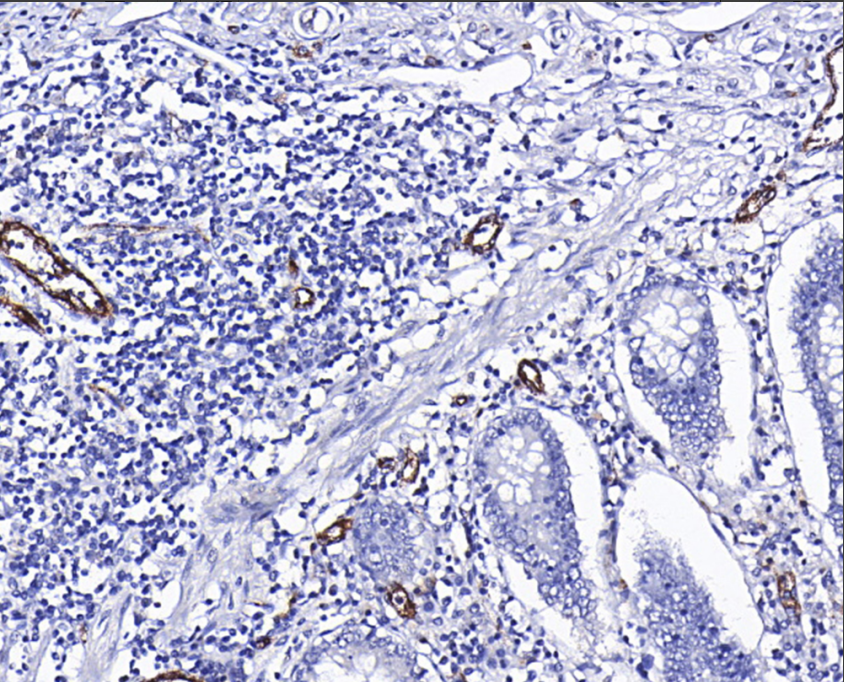

Human vascular hemophilic factor (VWF) is a 309 KDa multimeric plasma glycoprotein that plays an important role in maintaining hemostasis by forming a molecular bridge between the subendothelial collagen matrix and the platelet-surface receptor complex GPIb-IX-V, which promotes platelet adhesion to the site of vascular injury VWF can also act as a molecular chaperone for coagulation factor VIII by delivering it to the site of injury to stabilize its heterodimeric structure and protect it from premature plasma clearance. VWF also acts as a molecular chaperone for coagulation factor VIII, delivering it to the site of injury, stabilizing its heterodimeric structure and protecting it from premature plasma clearance. VWF is synthesized by endothelial cells and has been reported to be expressed in many tumors of vascular origin. IHC results contribute to the classification of acute myeloid leukemia FAB type M7, angiosarcoma and epithelioid hemangioendothelioma.

VWF antibody reagents can specifically bind to VWF molecular antigens. Immunohistochemistry kits containing VWF antibody reagents are suitable for the auxiliary diagnosis of acute myeloid leukemia FAB type M7, angiosarcoma, and epithelioid hemangioendothelioma.